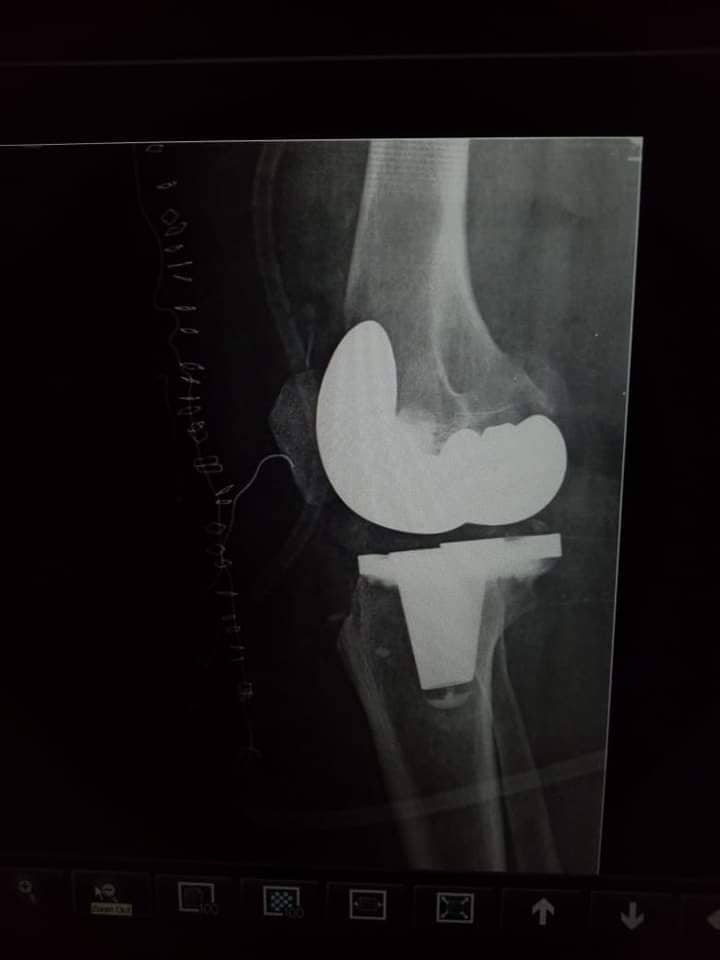

نجح الفريق الطبي بقسم جراحة العظام بمستشفي أبو حماد المركزي، محافظة الشرقية الساعات الماضية في إجراء جراحة متقدمة لتغيير مفصل ركبة كامل،وذلك بقرار علاج على نفقة الدولة، تحت إشراف الدكتور أحمد عباس مدير المستشفى، حيث تم تغيير مفصل ركبة كامل بمفصل صناعي تشريحي أسمنتي، لمريضة تبلغ من العمر 49 عاما، تعاني من خشونة وتآكل متقدم برأس عظمة الساق.

وجاء ذلك بعد عمل الأشعات والفحوصات المعملية اللازمة، والمريضة الآن بحالة مستقرة، وتحت الملاحظة من قبل الفريق الطبي بالمستشفى.

وتمت الجراحة تحت إشراف الدكتور عمرو عبد العال رئيس قسم العظام بالمستشفى، والدكتور عصام غالي رئيس قسم التخدير، وبقيادة الدكتور إسلام شفيق استشاري جراحة العظام، وفريق الأطباء من أخصائيي العظام والتخدير (شادي المجيدي، محمد عيد، ابراهيم زلط، محمد مجدي، محمد وجيه).